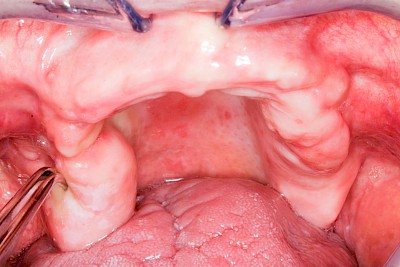

Überbein (Exostose)

Überbeine im Bereich der Kiefer sind gar nicht so selten. Häufiger im Bereich der Seitenzähne unterhalb des Zahnfleisches, aber auch in der Mitte vom Gaumen. Überbeine haben in dem Sinne keinen Krankheitswert, müssen also nicht operativ entfernt werden, wenn diese nicht stören. Überbeine können ein Anzeichen für Knirschen und Pressen sein.

In seltenen Fällen schwindet nur der Knochen, aber nicht die bedeckenden Schleimhäute. In diesen Fällen spricht man von einem sogenannten "Schlotterkamm".